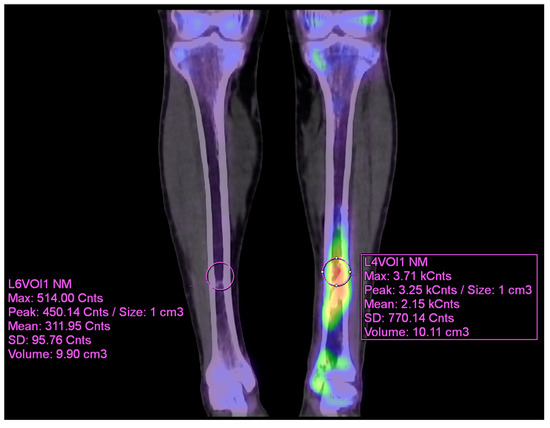

As the infection did not improve, the patient visited our outpatient clinic. He had been receiving intravenous and oral ciprofloxacin for 10 months since the 8-month postoperative day. After the initial visit to our clinic, 99mTc DPD bone SPECT/CT scan was performed, revealing areas of increased uptake, as shown in the images below (Figure 5 and Figure 6).

The patient then underwent surgery, during which extensive debridement was performed on the suspected infected intramedullary lesion. Tissue culture was also taken from the site with the highest uptake on the SPECT/CT scan. Some intramedullary bone marrow was also removed. Antibiotic-impregnated bone cement was inserted into the debrided area.

Figure 6. VOI (volume of interest) analysis of preoperative 99mTc DPD bone SPECT/CT coronal image (contralateral side and affected side) using Syngo.via.